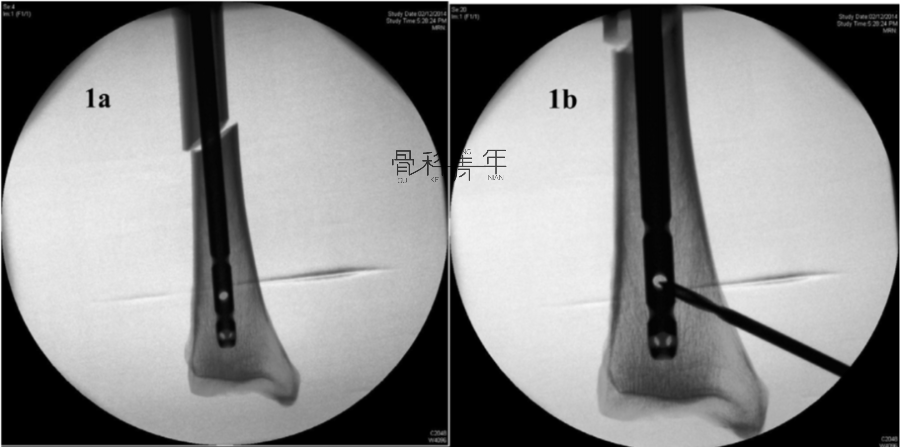

例1:

1a-1b:胫骨中段骨折采用髓内钉固定。可见置入主钉后骨折对线不良,存在侧方移位及成角畸形。

1c-1d:在骨折端成角平面,即冠状面上,拟置入阻挡螺钉部位近端钻孔,拧入松质骨螺钉,推动骨皮质与主钉移位,纠正侧方移位。

1e-1f:在松质骨螺钉置入后,可见端骨折端移位纠正,对线良好,复位后置入阻挡钉,维持复位。